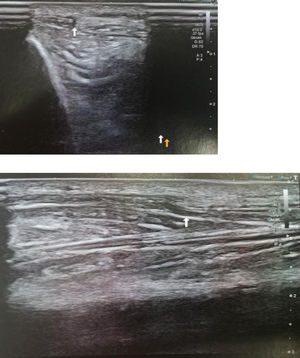

Material y métodosPaciente de 34 años, albañil, que en contexto de accidente laboral (caida de 2 metros) presenta contusión en cara lateral de pierna derecha con diagnóstico de fractura de 1/3 medio de perone de pierna derecha, Paciente presenta buen curso clinico con consolidación completa de la fractura a los 3 meses de evolución, pero persistiendo dolor y aumento de volumen en cara anterior de la pierna. Se solicita resonancia magnética de pierna que es informada como normal. A la exploración en reposo nada a destacar, en bipedestación (Fig. 1) se observa masa palpable de 2 cm aprox en cara anteromedial de 1/3 medio de tibia de pierna derecha, que se reduce al pasar a decúbito supino. Se realiza ecografia dinámica con paciente en bipedestación y forzando dorsiflexión del pie, confirmándose hernia de músculo tibial anterior con disrupción parcia de su fascia, hernia de 11,7 mm de tamaño con 3 cm de extensión (Fig 2). Se realiza tratamiento conservador mediante tratamiento rehabilitador antiinflamatorio (magnetoterapia) + vendajes compresivos locales.

Case report34-Year-old patient, bricklayer, who in the context of an accident at work (2-m fall) presented with a contusion on the lateral aspect of the right leg with a diagnosis of fracture of proximal fibula, who underwent conservative treatment with analgesics and partial weight bearing with 2 crutches. Patient have good clinical course with complete consolidation of the fracture at 3 months, but pain and increased volume persisted in the anterior aspect of the leg. Local examination revealed no obvious swelling in the leg at rest, with patient lying in the supine position, also no evidence of any sensorineural deficit or varicose veins. An MRI of the leg is requested and is reported as normal. Patient insists that he is quite well at rest but when he stand he presents pain and also “a palpable mass”. On standing and straining the leg muscles, there was a soft, non-tender swelling, measuring approximately 2cm, seen along the anterior aspect of the leg in its mid-part standing (Fig. 1), and reduced in supine. Dynamic ultrasound was performed with a patient standing and forcing dorsiflexion of the foot, confirming herniation of the anterior tibial muscle with partial disruption of its fascia, a hernia of 11.7mm in size with a 3-cm extension (Fig. 2). Conservative treatment is carried out by our rehabilitation team with anti-inflammatory treatment (magnetotherapy)+local compression with bandages.

DiscussionMuscle hernias are focal herniations of muscle tissue through a defect in its fascial sheath. They are most commonly found in the lower extremity. They are mostly underdiagnosed or misdiagnosed as muscle hematomas and varicosities.1 There are about 200 cases of muscle hernias described in the literature. In 1929, Hugo Ihde reported a case series of 12 patients with muscle hernias along with their classification.2 Ihde divided muscle hernias into two groups: traumatic and constitutional. Constitutional or congenital hernias occur due to weakness in muscle fascia after chronic stress. It has been proposed that there are fenestrations in the muscle compartments through which perforating veins enter. Due to chronic stress, the fenestrations enlarge and eventually muscle hernias bulge through these openings.3 Traumatic or acquired hernias are seen secondary to penetrating trauma, direct trauma causing closed fracture with fascial tear and indirect trauma (force applied to contracted muscle causing fascial rupture).4 The anterolateral tibial compartment is the commonest site due to being a superficial and tight fascial compartment.5 A high index of suspicion and awareness of a muscle hernia helps in its early diagnosis. In the lower extremity, tibialis anterior muscle hernia is found most frequently due to the vulnerability of its fascia to trauma. The other muscles affected in the lower extremity are extensor digitorum longus, peroneus longus, peroneus brevis and gastrocnemius.6 In our case, there was a history of blunt trauma to the leg 4 years before that might have contributed to muscle hernia. On clinical examination, muscle hernia may present as a palpable bulge, soft tissue mass or subcutaneous nodule. The muscle typically herniates during leg dorsiflexion, also known as “fencer's lunge” position.7 The swelling reduces when the patient is supine or the muscle is relaxed. Although the clinical picture points towards the diagnosis, imaging, especially ultrasound, should be used to confirm it. The differential diagnosis of muscle hernias includes varicosities, angiomas, arteriovenous malformation, lipomas, ruptured muscle (a pseudohernia) and soft tissue tumours.4 However, these tumours do not show movement on changing the patient position. Dynamic sonography is diagnostic in detecting a myofascial defect and can confirm the diagnosis. Dynamic sonography can detect a muscle bulge through the fascial defect on muscle contraction and its retraction on relaxation. Sonography is advantageous as it is a real-time modality, so that muscle herniation is detected during a dynamic examination, and the nature of lesion can be shown to the patient, which is reassuring. The examination is done in a standing position or by contracting the muscle.8 A 3D scan allows for a better delineation of fascial defects with a proper placement of the reference point. A 3D scan highlights the muscle herniation and makes hernia easy to see.9 MRI is useful in equivocal USG findings and confirms muscle herniations with a better musculofascial demarcation.10 There is no ideal treatment for muscle herniations described in the literature. Most hernias are asymptomatic and require only reassurance. Mildly symptomatic hernias are treated conservatively with rest, restriction of exercise and the use of compression stockings. Various surgical techniques for symptomatic hernias include decompressive fasciotomy, primary fascial repair – including direct closure of the defect, closure of the defect using autologous or synthetic grafts, etc.11